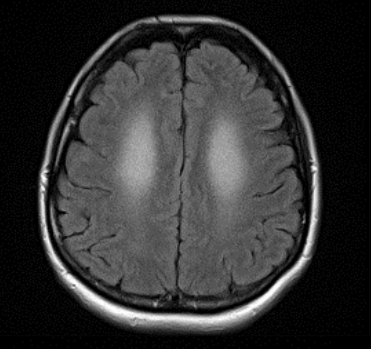

A 43-year-old woman with recently diagnosed hypothyroidism presented with a 3-month history of declining cognition, confusion, disorientation, and an inability to communicate or ambulate. She had become...